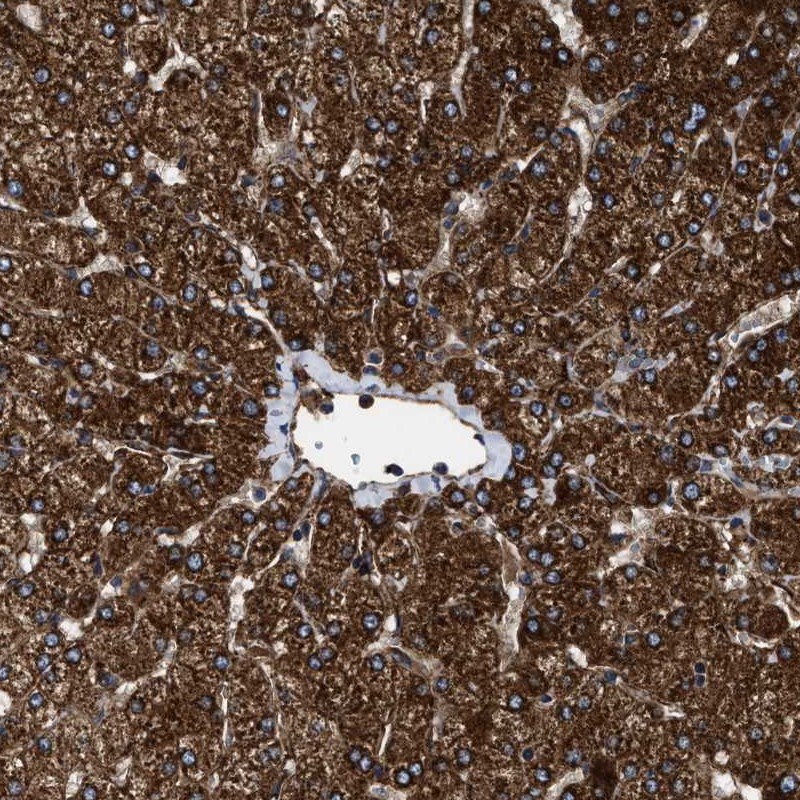

Immunohistochemical staining of human liver shows strong cytoplasmic positivity in hepatocytes.